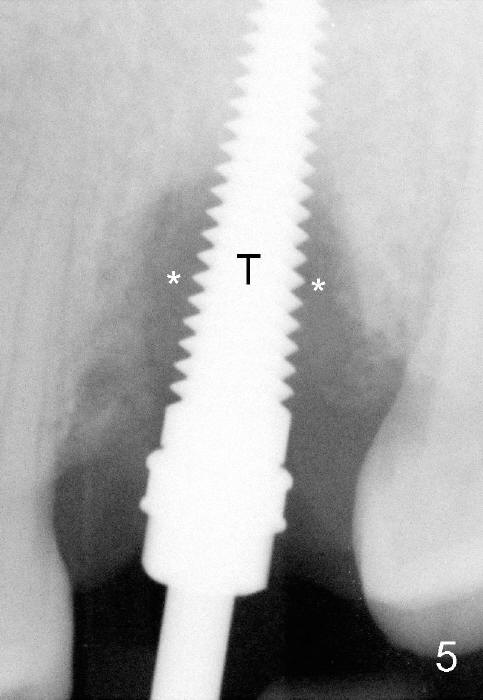

Bone density around the molars (including apical to #14) (Fig.1 black *) is higher than that around the premolar (white *). In fact the tooth has horizontal root fracture (Fig.2: <: CEJ), consistent with high bone density (strong mastication). An immediate implant is planned (Fig.3). After extraction, osteotomy starts at the buccal slope of the palatal (Fig.4 P) socket. Because of high bone density apical to the sockets, drills are required for osteotomy in the septum (type II bone) instead of osteotomes and primary stability is easily achievable (>60 Ncm). When a 7 mm implant (Fig.6 I)) is placed, the peri-implant gaps are much smaller (*) than that with a 4.5 mm tap (Fig.5 T). This helps bone grow faster toward implant. A long implant (17 mm) is necessary for this case to obtain primary stability in the apical one (double arrows in Fig.6). With reamers, a fair amount of autogenous bone is harvested during drilling, mixed with allograft and synthetic bone and placed in the remaining buccal (Fig.7) and palatal (Fig.8) sockets. The openings of the buccal and palatal sockets are covered with collagen dressing (C) and perio dressing. The latter is kept in place by a short abutment (Fig.6-8 A).